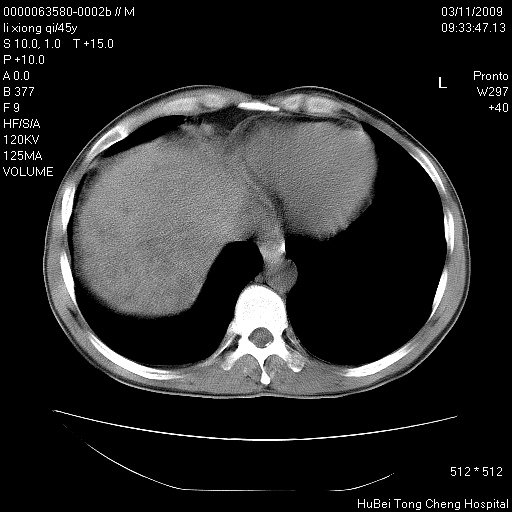

患者 男,45岁。胸痛,咳嗽伴痰中带血1月余。

临床诊断:肺结核?

胸部ct轴位平扫(层厚10mm,螺距1.5,重建间隔10mm),图像如下:

考虑肝癌肺转移